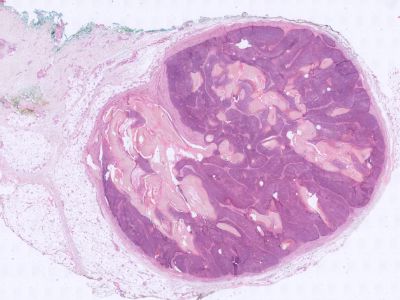

Histologie:Het histologisch beeld wordt gekenmerkt

door een scherp afgrensbare tumor in de diepe dermis, veelal rijkend tot in

de subcutis (1,2). Twee typen cellen zijn karakteristiek voor het pilomatrixoom.

In de periferie liggen basofiele cellen, welke keratiniseren en richting het

centrum overgaan in eosinofiele ghost cells. De basofiele cellen hebben een

hyperchromatische kern, nauwelijks cytoplasma en vertonen veel mitosen. Ze lijken

op de cellen bij het basaalcelcarcinoom (1-3). De centraal gelegen ghost cells

hebben een opheldering ter plaatse van de verdwenen kern, zijn groter en hebben

meer cytoplasma. Naarmate de laesie ouder wordt, neemt het aantal basofiele

cellen af en nemen de ghost cells in aantal toe. In 20% van de gevallen zijn

er bij excisie van het pilomatrixoom helemaal geen basofiele cellen meer aanwezig.

De tumor wordt vaak omgeven door een lymfocytair infiltraat en meerkernige reuscellen

(1,3,4). In ruim twee derde van de tumoren treedt calcificatie op en in ruim

10% ook ossificatie. De epidermis vertoont meestal geen afwijkingen (1,2).